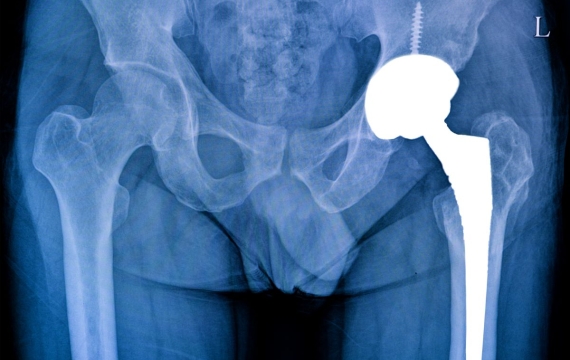

El cirujano traumatólogo en la cirugía articular logra extraer una articulación que se encuentra dañada, se trata, pues, de un procedimiento de reemplazo donde el especialista en traumatología coloca una nueva pieza artificial, para lograr juntar dos o más huesos, tal como: la cadera, hombro y rodilla. Las articulaciones artificiales son hechas en cobalto, titanio o cromo, esto junto con plásticos que son de una densidad alta.

Reemplazo articular o artroplastia protésica

Con esta técnica se reemplaza de manera parcial o total una articulación con una prótesis o un implante artificial.